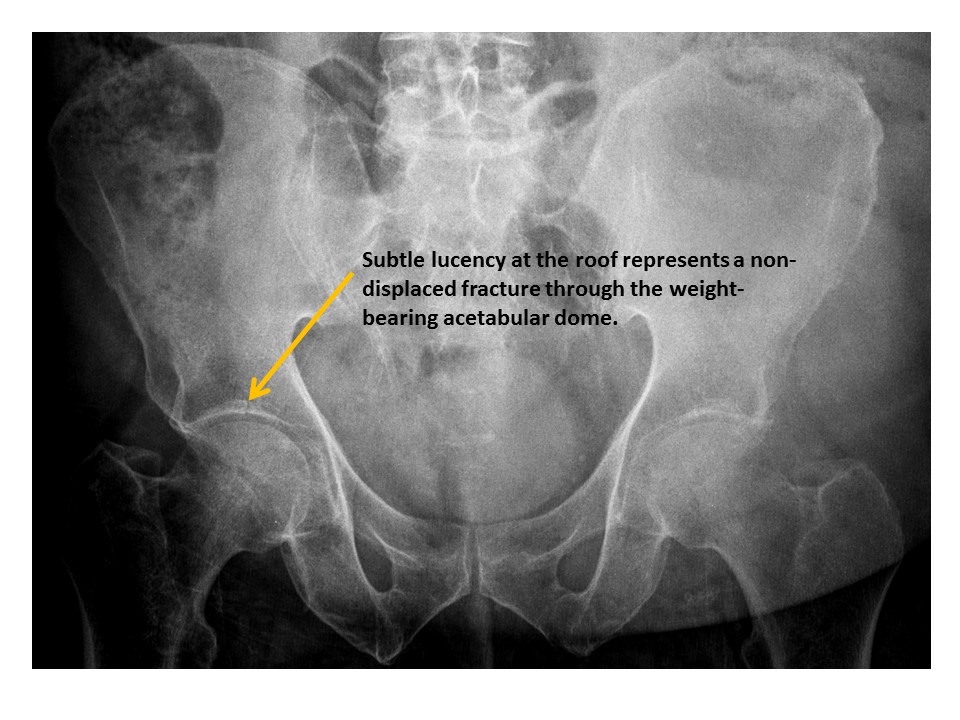

Acetabular roofs are discontinuous. [Yes/No]

HIPS/PROXIMAL FEMURS

1-Hip/pelvis fracture/malalignment as discussed above.